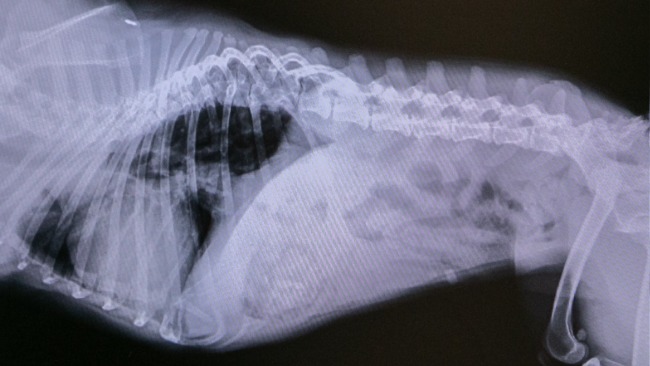

Na badaniu RTG wykryto również niepokojącą zmianę, która wymaga pilnej dalszej diagnostyki. Przed nami kolejne badania, by sprawdzić, z czym dokładnie się mierzymy i jak możemy jej pomóc.

Lista koniecznych działań jest długa: korekta płatków nosowych, być może i podniebienia, dalsza diagnostyka zmiany z RTG, badanie serca, testy, szczepienia, zabezpieczenie przeciw pasożytom.